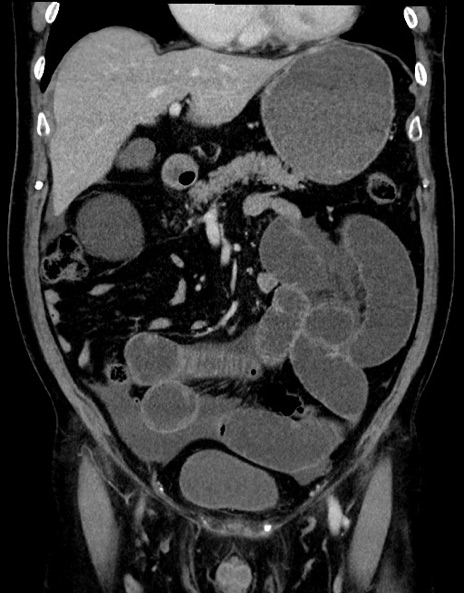

症例15(冠状断像)

【症例】70歳代男性

【主訴】腹痛

【現病歴】今朝から腹痛あり。全体的に痛い。特に左上の方。排ガスが今日はない。冷や汗が出る。

【既往歴】直腸癌術後

【身体所見】左側腹部〜上腹部に圧痛あり。腹膜刺激症状明らかなではない。軽度反跳痛。左下腹部に術後瘢痕あり。

【データ】WBC 7700、CRP 0.02